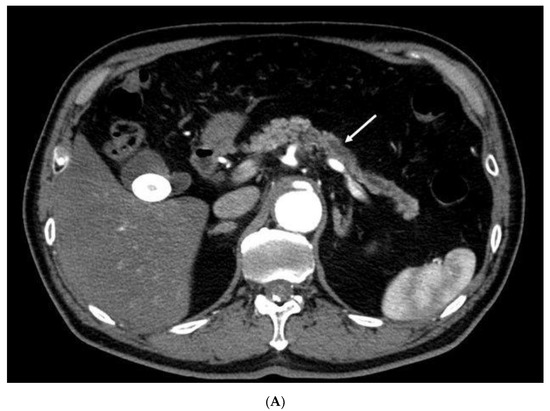

- Sakamoto, H.; Kitano, M.; Suetomi, Y.; Maekawa, K.; Takeyama, Y.; Kudo, M. Utility of contrast-enhanced endoscopic ultrasonography for diagnosis of small pancreatic carcinomas. Ultrasound Med. Biol. 2008, 34, 525–532. [Google Scholar] [CrossRef]